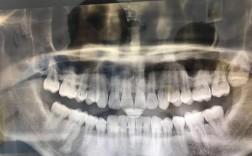

我理解你对牙齿正畸拍片角度过大的担忧,这确实是一个需要认真对待的问题,角度过大意味着拍摄时患者的头部位置没有按照标准要求摆放,导致影像出现偏差或失真,这种偏差可能看似微小,但在正畸诊断中却可能产生连锁反应,📸角度过大可能带来的主要影响影像...